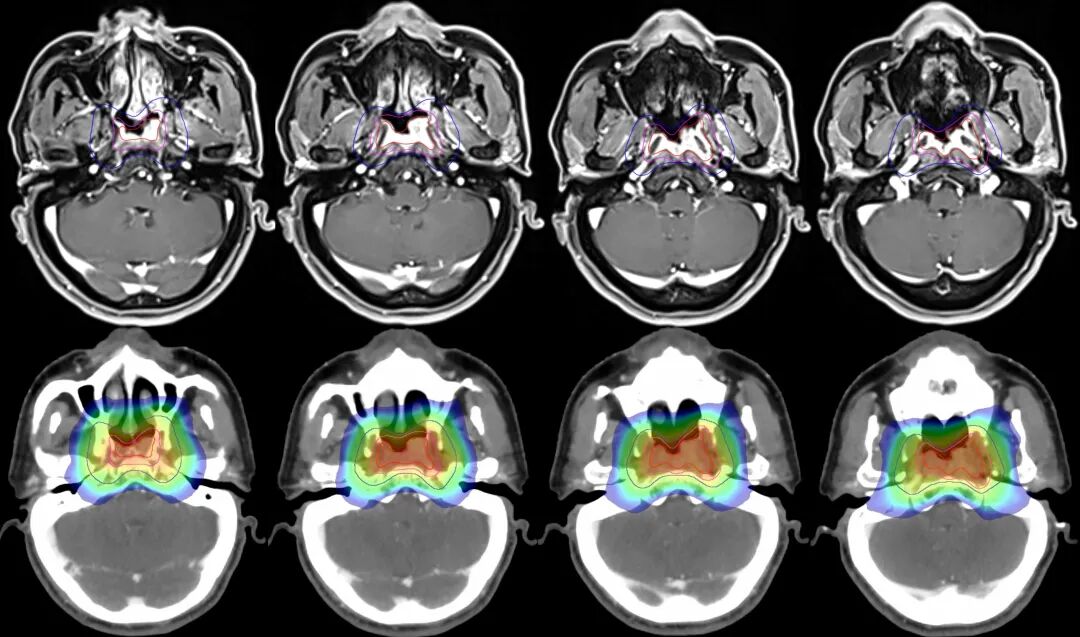

病例5:42歲男性患者,左側(cè)耳悶起病。核磁檢查可見鼻咽腫物,(侵犯雙側(cè)頭長肌、左側(cè)腭帆張肌、腭帆提肌及左側(cè)咽旁間隙、枕骨斜坡、蝶骨體)為局部晚期鼻咽癌,伴多發(fā)雙側(cè)頸部淋巴結(jié)轉(zhuǎn)移。(左側(cè)咽旁間隙、左側(cè)頸部腫大淋巴結(jié),雙側(cè)頜下、右側(cè)頸動(dòng)脈鞘區(qū)及下頸部淋巴結(jié))

圖注:治療前后比對(duì)。上排為治療前,可見鼻咽腫物主要位于左側(cè)鼻咽部,局部侵犯非常嚴(yán)重。下排為治療后,鼻咽區(qū)腫瘤病灶完全消失。

圖注:上排紅線內(nèi)為腫瘤照射靶區(qū)。下排為劑量分布圖,可見中心區(qū)高劑量照射,周邊劑量快速跌落,形成銳利的集束聚焦照射,周圍重要器官得到良好保護(hù)。